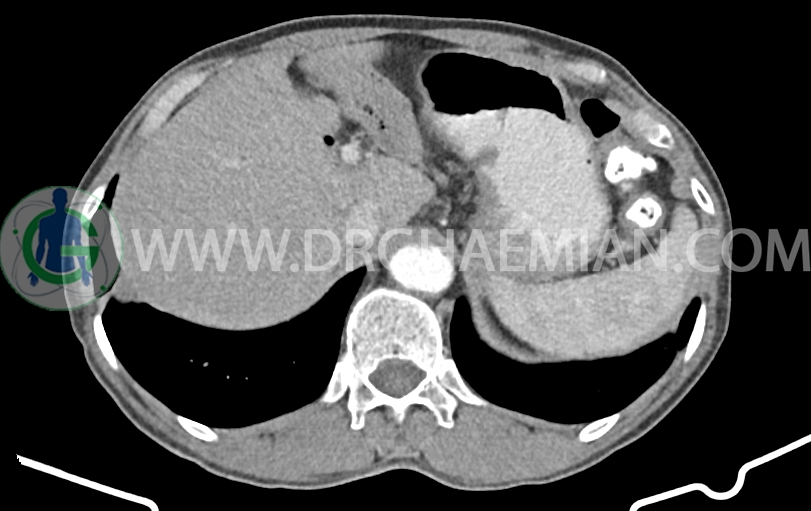

لنف نود به ابعاد mm 14×10 در مجاورت origin SMA دیده می شود. (بدون تغییر نسبت به سی تی اسکن قبلی)

شواهد جراحی ویپل به صورت partial pancratectomy و کوله سیستکتومی و همچنین گاستروژژنوستومی و پانکراتیکوژژنوستومی – هپاتوژژنوستومی مشهود است .

MPD دیلاته به قطر 8mm (حاوی استنت می باشد)

body پانکراس کمی کوچک و اتروفیک است